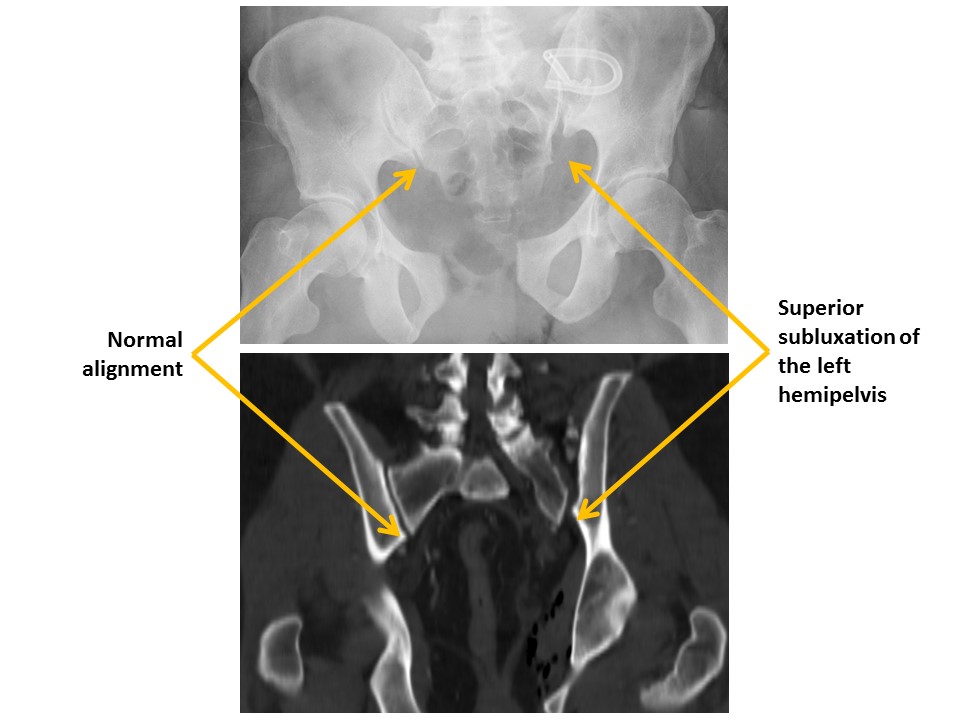

The sacroiliac joints are widened and asymmetric. [Yes/No]

There is vertical subluxation of the sacroiliac joints. [Yes/No]

Hip alignment is abnormal. [Yes/No]

1-Hip/pelvis fracture/malalignment as discussed above.